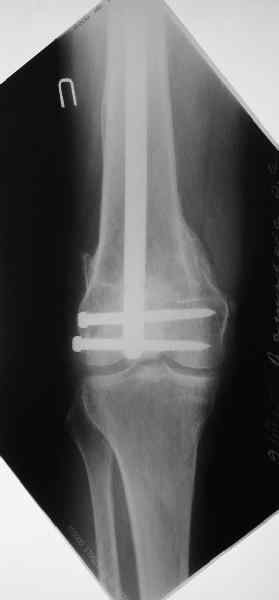

Re: Многооскольчатый перелом бедраa

Чтобы больной не смог сгибать колено, выстоять в сустав железо должно побольше значительно, чем на 1 мм. В приложении снимок с выстоянием ммм на 3, видна и функция колена. Хотя клиника импинджмента была, но даже не на один восклицательный знак. После удаления стержня проблемы и вовсе рассосались.